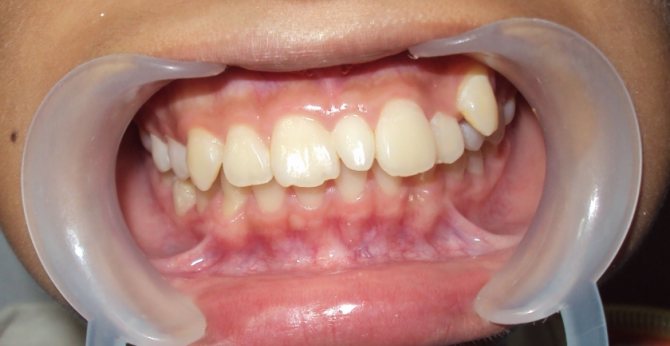

Если у детей лишние зубы

Сверхкомплектные зубы у детей появляются в постоянном прикусе и именно на передней группе — вместо 4 резцов верхней или нижней челюсти может появляться 5 и более. Обычно появление таких зубов становится причиной смещения соседних, правильно расположенных зубов. В остальном дети не предъявляют никаких жалоб.

Всем известно, что в ротовой полости должно находиться 32 зуба, это считается нормой. К аномалии количества зубов относится их избыточное количество, а также недостаток или полное отсутствие. Первая проблема имеет название – гипердонтия, и для нее характерно наличие сверхкомплектных зубов, которые находятся не в зубном ряду, а за его пределами и сильно смещают своих соседей в стороны, тем самым, меняя их нормальное положение на патологическое. Сверхкомплектные зубы чаще можно обнаружить на верхних рядах, их размеры и форма не совпадают с принятыми нормами. Довольно редко случается так, что сверхкомплектный зуб удачно втиснулся в зубной ряд.